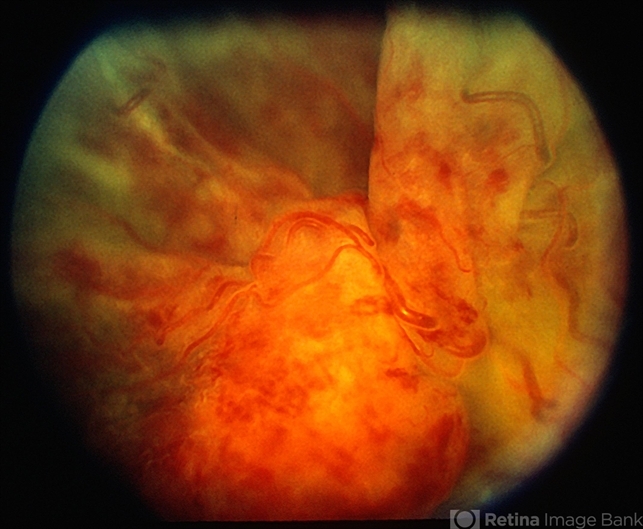

By From the Collections of Thomas M. Aaberg, MD and Thomas M. Aaberg Jr., MD

- meningioma

- Central retinal vein occlusion and retinal detachment.